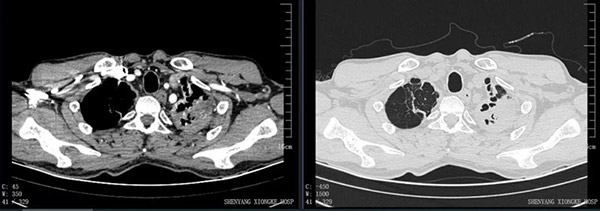

入院后经全面检查,考虑张先生左肺上叶结核合并感染(霉菌?)、双肺上叶支气管扩张、左肺上叶毁损肺。 为防止再出血及大咯血以致危及生命,手术切除已经没有功能且反复引起咯血的左上叶毁损肺是必然的。

左肺呈无功能状态,重要大血管(锁骨下动、静脉)与病灶粘连紧密。这样的肺切除极易出现血管破裂、大出血。

至此层面,整个左肺基本无功能,解剖层次不清晰。血管、支气管扭曲、变形,再次提高手术难度。